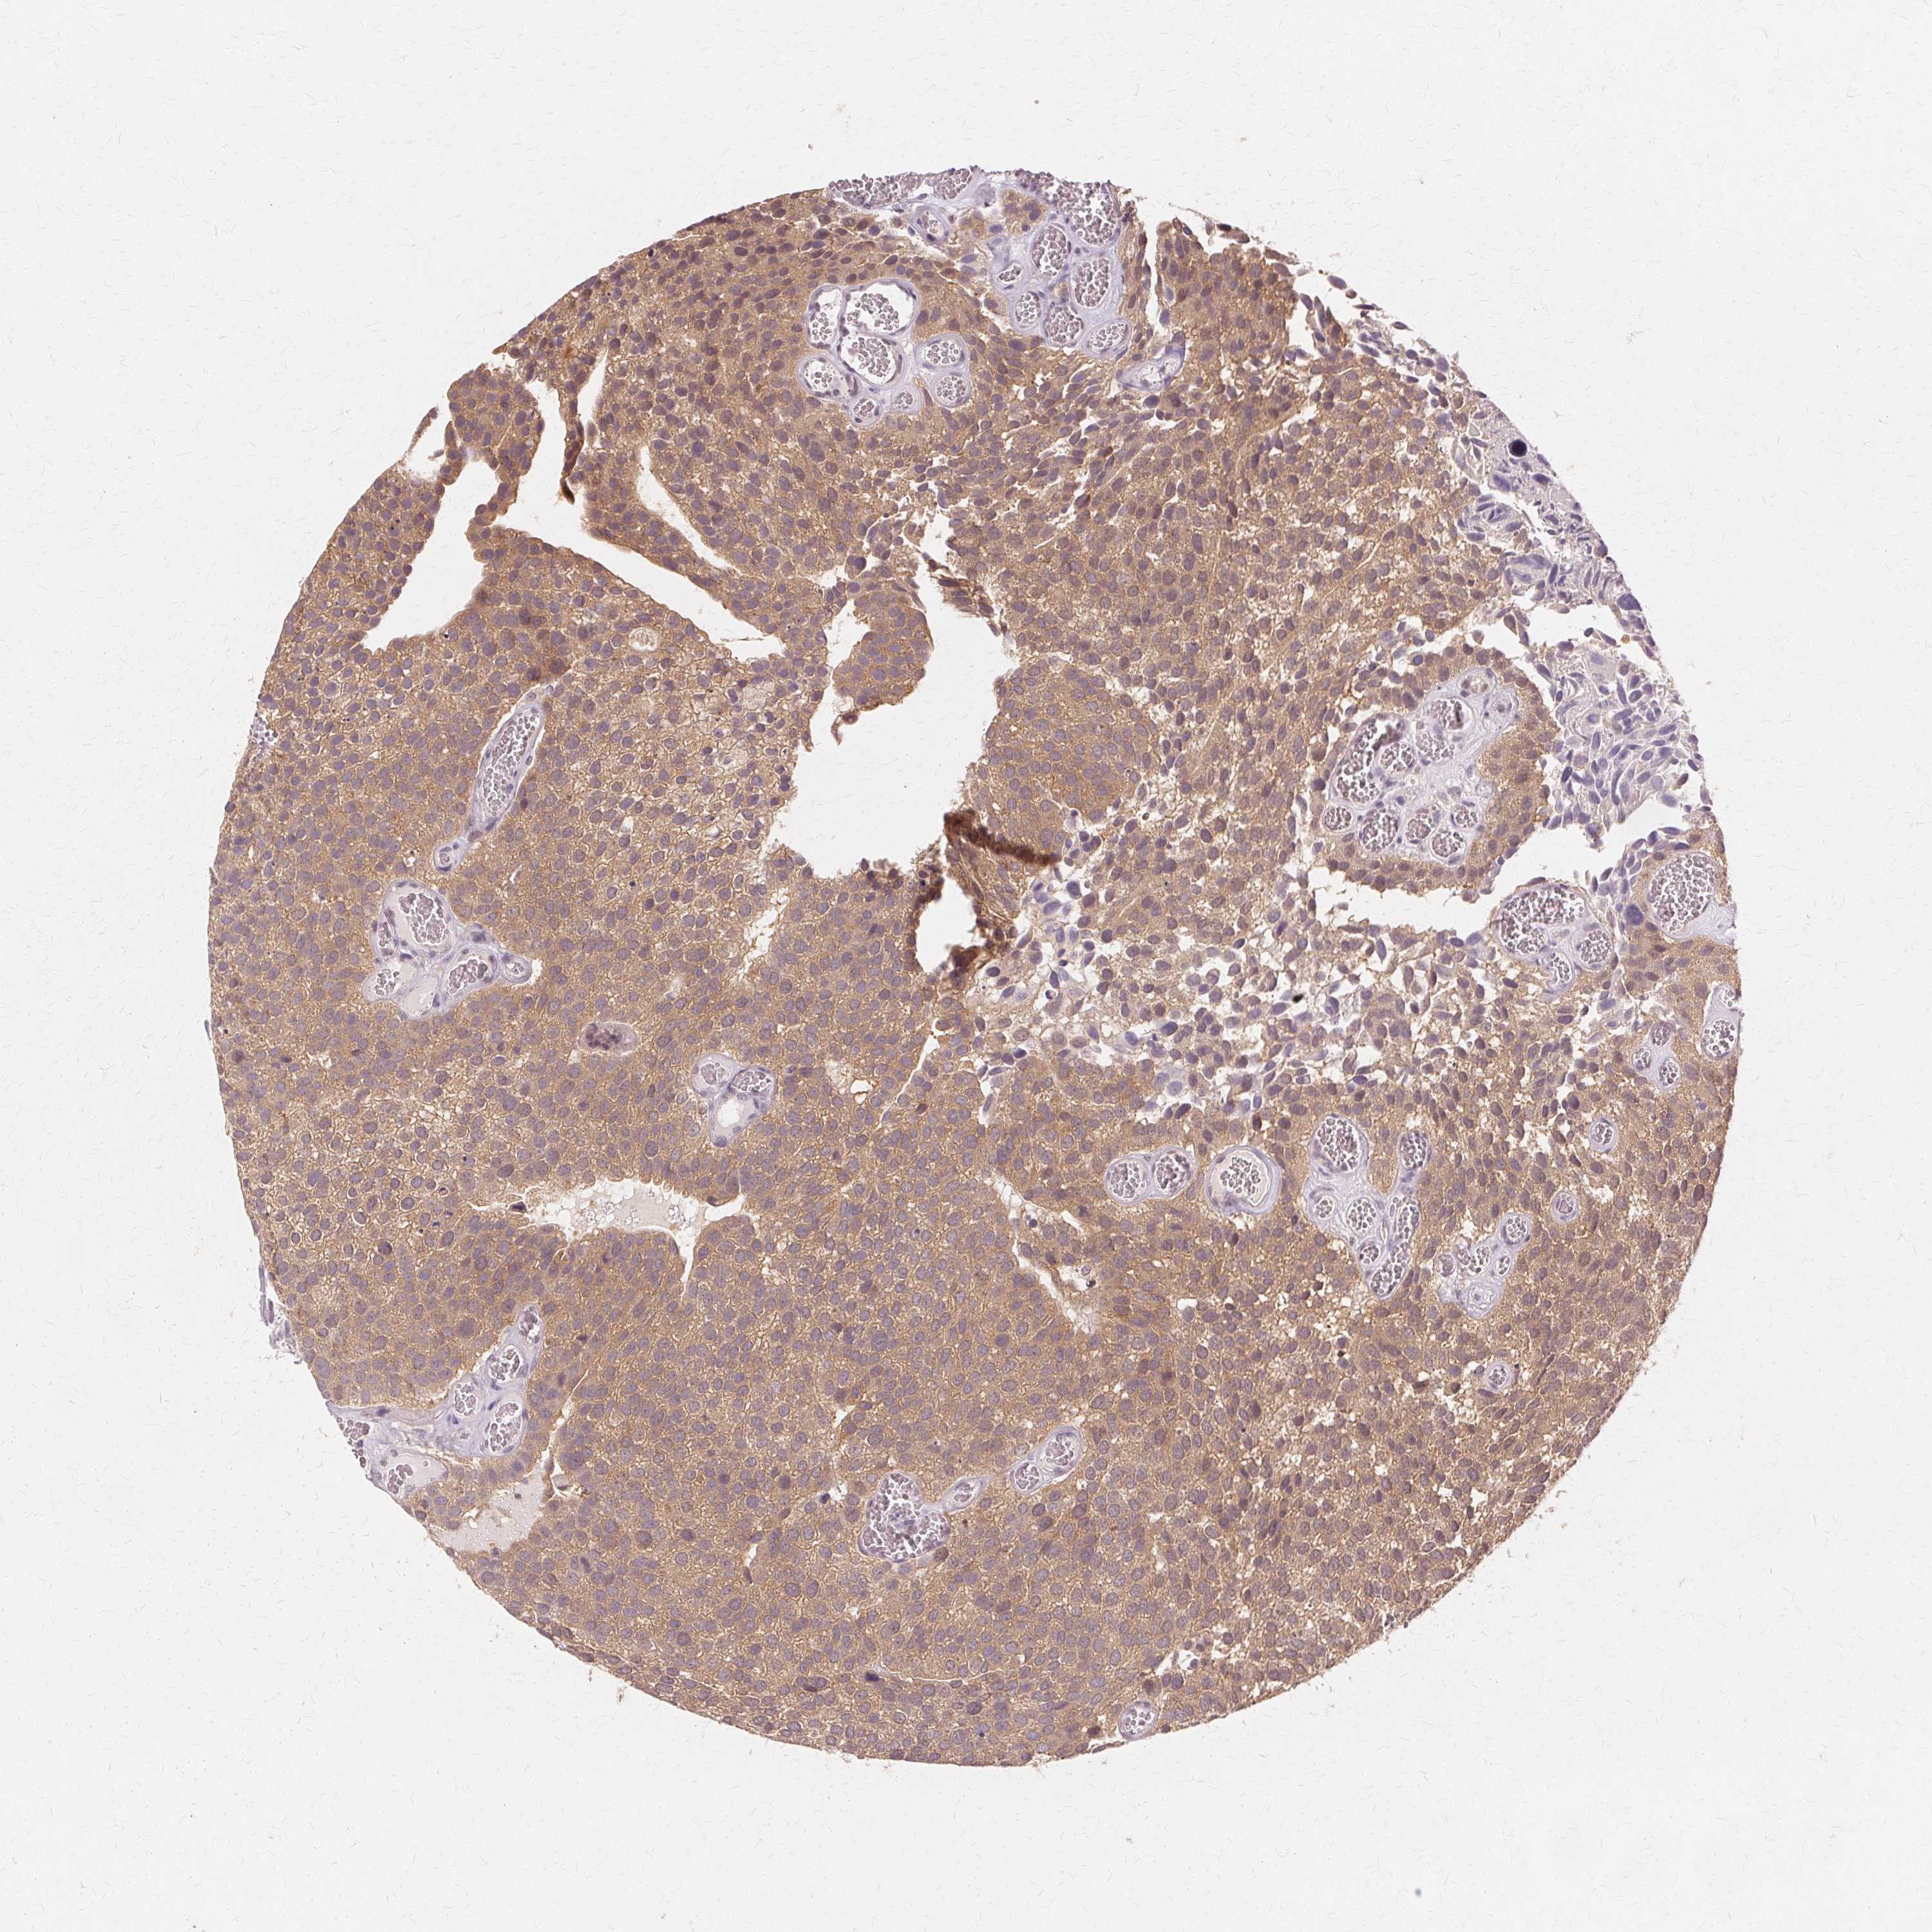

UROTHELIAL CANCER - Protein expressioni

A mouse-over function shows sample information and annotation data. Click on an image to view it in a full screen mode. Samples can be filtered based on level of antibody staining by selecting one or several of the following categories: high, medium, low and not detected. The assay and annotation is described here.

Note that samples used for immunohistochemistry by the Human Protein Atlas do not correspond to samples in the TCGA dataset.

Antibody stainingi

Antibody staining in the annotated cell types in the current human tissue is reported as not detected, low, medium, or high, based on conventional immunohistochemistry profiling in selected tissues. This score is based on the combination of the staining intensity and fraction of stained cells.

Each image is clickable and will lead to virtual microscopy that enables deeper exploration of all samples and also displays staining intensity scores, fraction scores and subcellular localization as well as patient and tissue information for each sample.

Antibody HPA005525

Antibody HPA064708

Antibody CAB012459

Staining

High

Medium

Low

Not detected

Intensity

Strong

Moderate

Weak

Negative

Quantity

>75%

75%-25%

<25%

None

Location

Nuclear

Cytoplasmic/membranous

Cytoplasmic/membranous,nuclear

Urothelial carcinoma, NOS